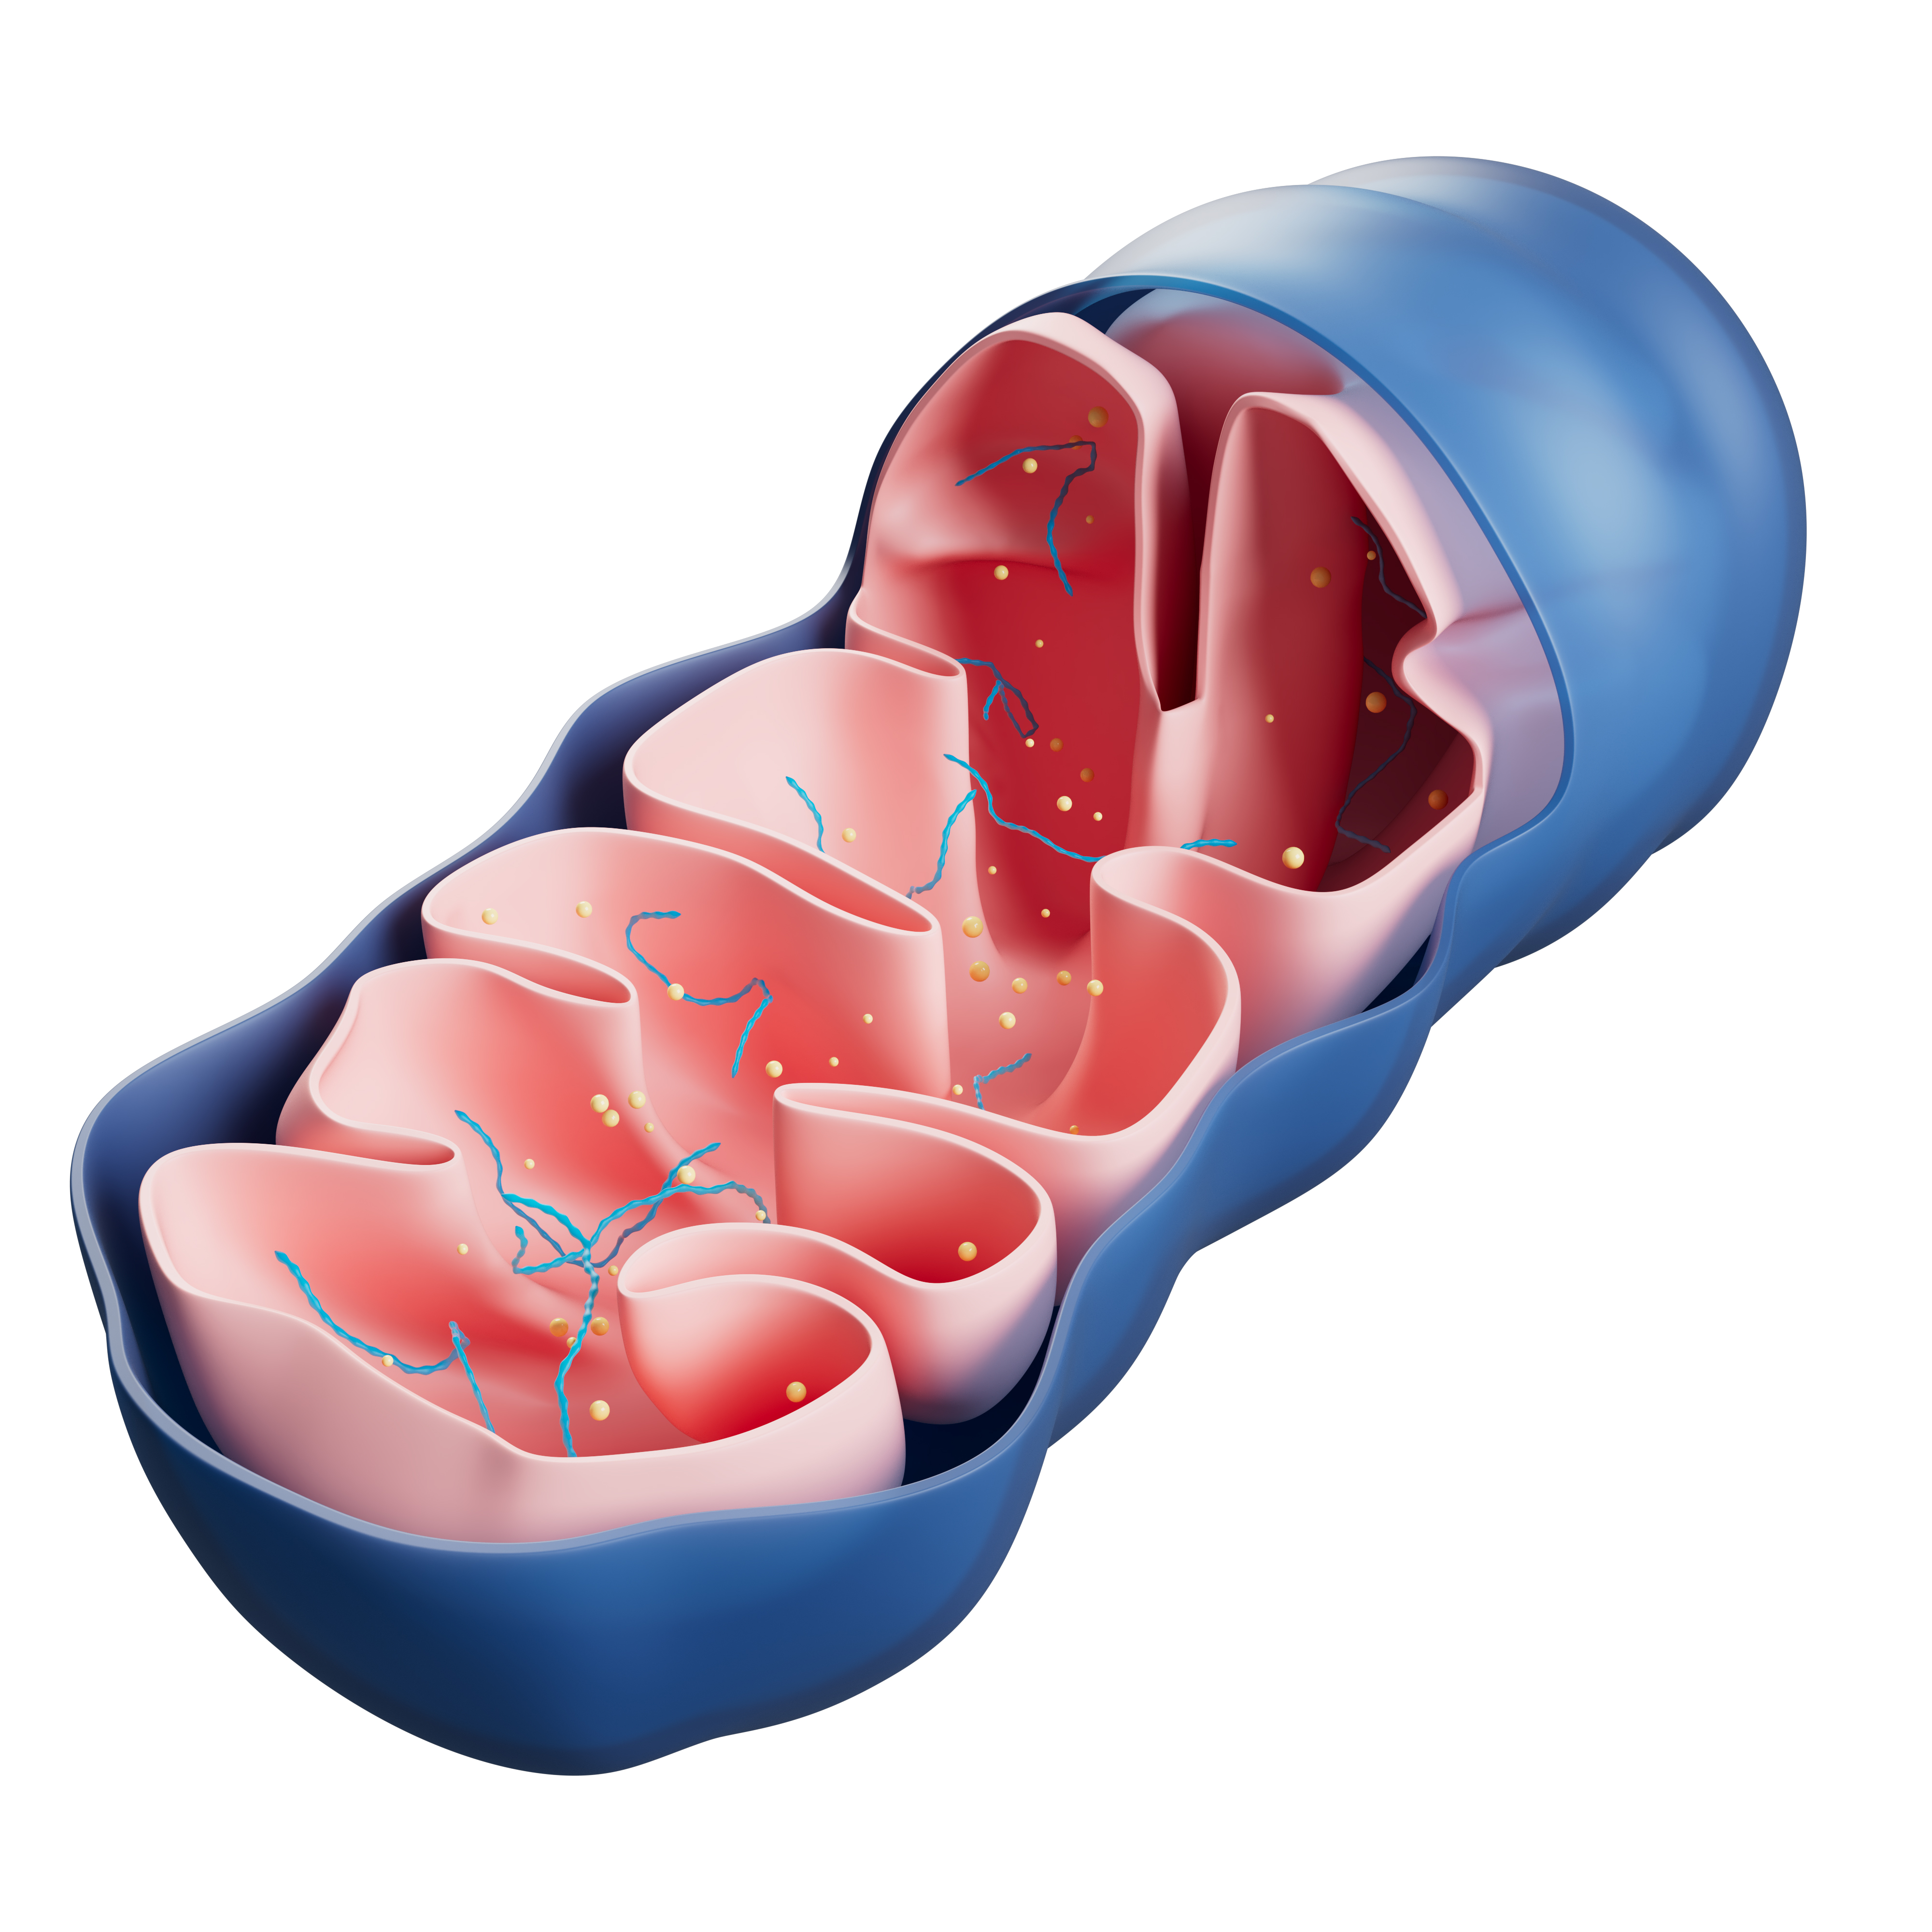

Importancia en la Optimización Mitocondrial

La energía que sientes diariamente proviene en gran parte de tus mitocondrias. El azul de metileno se destaca al mejorar la función mitocondrial. Investigaciones recientes sugieren que puede aumentar la eficiencia en la producción de energía a nivel celular.

Esto significa que podrías experimentar más energía a lo largo del día. La mejora en la función mitocondrial puede traducirse en un mejor rendimiento físico y mental. Si buscas una manera de sentirte revitalizado, el azul de metileno podría ser la respuesta. Descubre cómo integrarlo en tu rutina.